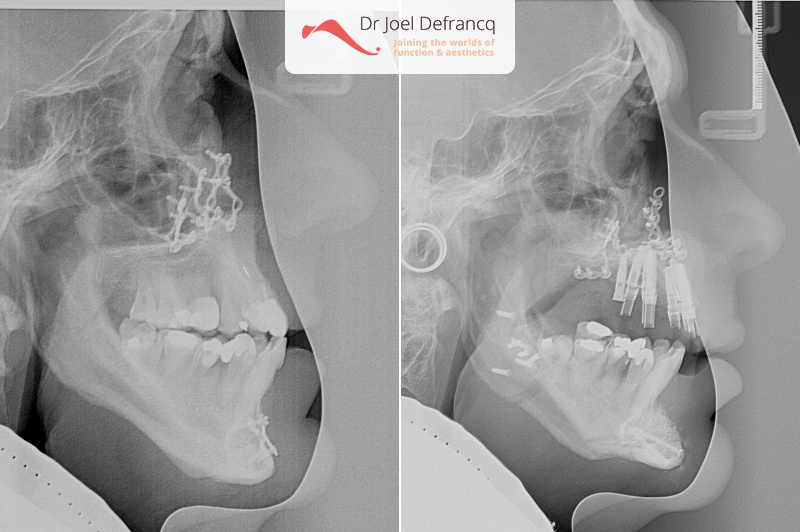

Dentale diagnose

- Klasse III

Kaakchirurgie

- Verlenging onderkaak (BSSO)

- Verlenging bovenkaak (Le Fort I)

- Kinchirurgie

- Verbreden bovenkaak (Smile distractor)

Behandeling tandheelkundige implantaten

- Vaste tanden op implantaten (bovenkaak)

- Implantaten met osteotomie

- Implantaten met beenopbouw